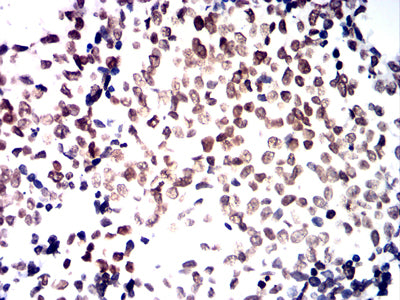

分类: 科研抗体货号: 32329别名: LCA; LY5; B220; CD45; L-CA; T200; CD45R; GP180应用: IHC,FCM反应种属: Human